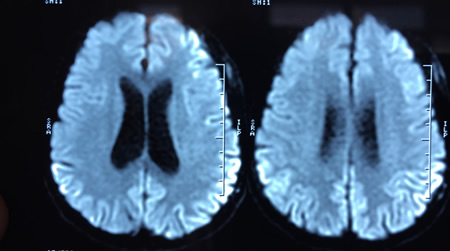

RNM cranioencefálica: o sinal pulvinar (um termo que se refere à hiperintensidade pulvinar bilateral) em um paciente com doença de Creutzfeldt-Jakob em imagens ponderadas por difusão

Do acervo pessoal de Leo H. Wang; usado com permissão